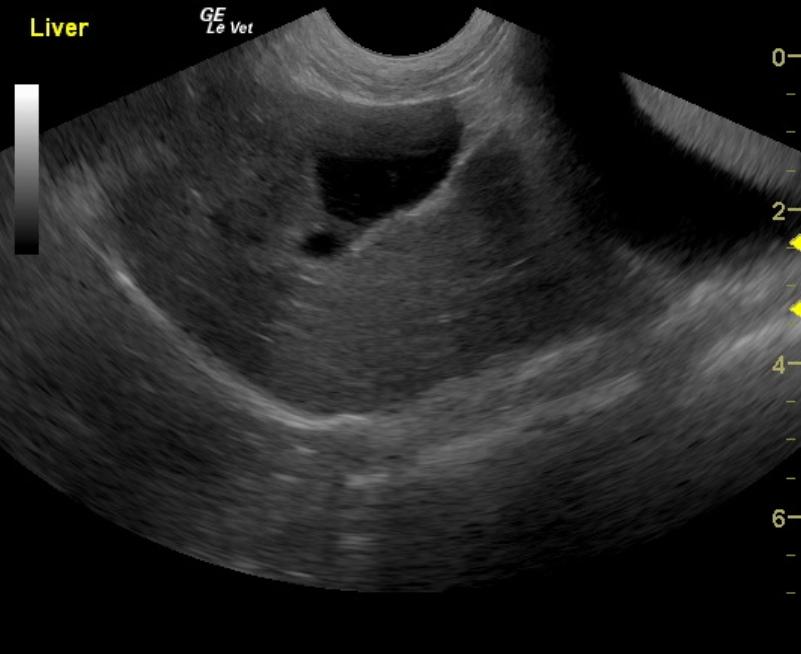

Image Interpretation

Deep right liver mass impinging upon the diaphragm and vena cava dorsally; the mass is likely not resectable. This is probably a cystadenoma, but adenocarcinoma is possible. A right perirenal cyst with a concurrent renal cortical cyst is noted in the right kidney. There is significant renal dystrophy of both kidneys, with pyelectasia or potential concurrent urinary tract infection.